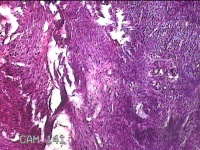

子宫肌瘤

性别

女

年龄

41岁

临床诊断

子宫肌壁间肌瘤

一般病史

发现子宫肌瘤4年余。

标本名称

大体所见

灰白色圆柱形条索状组织10.5x7x1.3㎝一堆,切面均为灰白色结节状或编织状,质硬。

图1